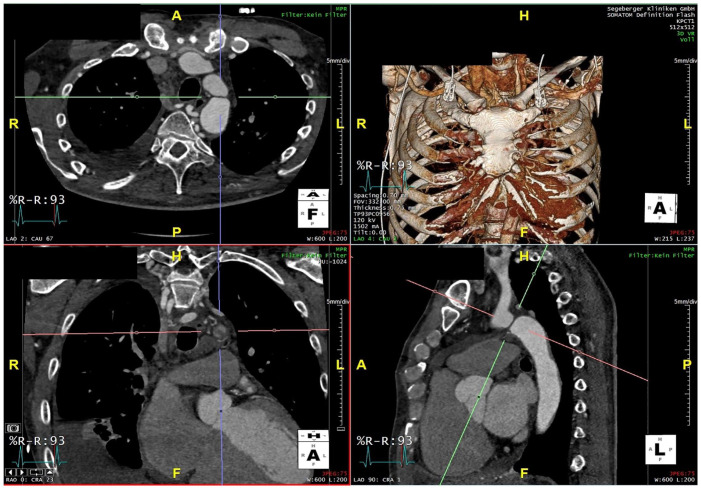

目的:对于成人主动脉缩窄,血管内修复是一种安全性可接受的治疗方法。主动脉峡部闭锁是一种与主动脉完全闭塞有关的情况,不允许在峡部进行导管插入术。本技术说明描述了使用射频和“带电导线技术”对主动脉峡部闭锁进行再通。技术:在远端选择性地去除PTFE(聚四氟乙烯)导丝,并通过主动脉峡部锁定远端的导管放置导丝。电线裸露的一端被夹在一支电外科铅笔上。通过将导线推向郁金香圈套器,郁金香圈套器通过左跨臂入路作为目标放置在闭塞物的近端,并在短时间内激活电外科铅笔,带电的导线使闭塞物重新通孔,并被圈套并用于引导球囊可膨胀覆盖支架的植入。结论:传统方法治疗成人主动脉峡部闭锁失败后,可采用钢丝穿刺技术进行再通。临床影响:在传统尝试失败后,带电导线技术提供了一种现成的选择,可以修改标准导丝,用于射频穿过完全主动脉峡部闭塞。这项新技术也可以应用于其他情况,如剥离皮瓣开窗、经腔入路等。

Purpose: For aortic coarctation in adults endovascular repair is the treatment of choice with an acceptable safety profile. Aortic isthmus atresia is a related condition with a complete occlusion of the aorta not allowing catheterization across the isthmus. This technical note describes a recanalization of an aortic isthmus atresia using radiofrequency with an "electrified wire technique."

Technique: A guidewire was selectively denuded of PTFE (polytetrafluoroethylene) at the distal end and was placed through a catheter distal to the aortic isthmus atresia. The denuded end of the wire was clamped to an electrosurgery pencil. By pushing the wire toward a tulip-snare, which was placed as a target proximal of the occlusion via left trans-brachial access, and shortly activating of the electrosurgery pencil the electrified wire recanalized the occlusion and was snared and used to guide implantation of a balloon-expandable covered stent.

Conclusion: The electrified wire puncture technique can be used to recanalize adult aortic isthmus atresia after failed conventional attempts.Clinical ImpactThe electrified wire technique offers an off-the shelf option to modify standard guidewires for the use with radiofrequency to cross a complete aortic isthmus occlusion after failed conventional attempts. This new technique may be applied also in other situations like dissection flap fenestration, transcaval access and similar.